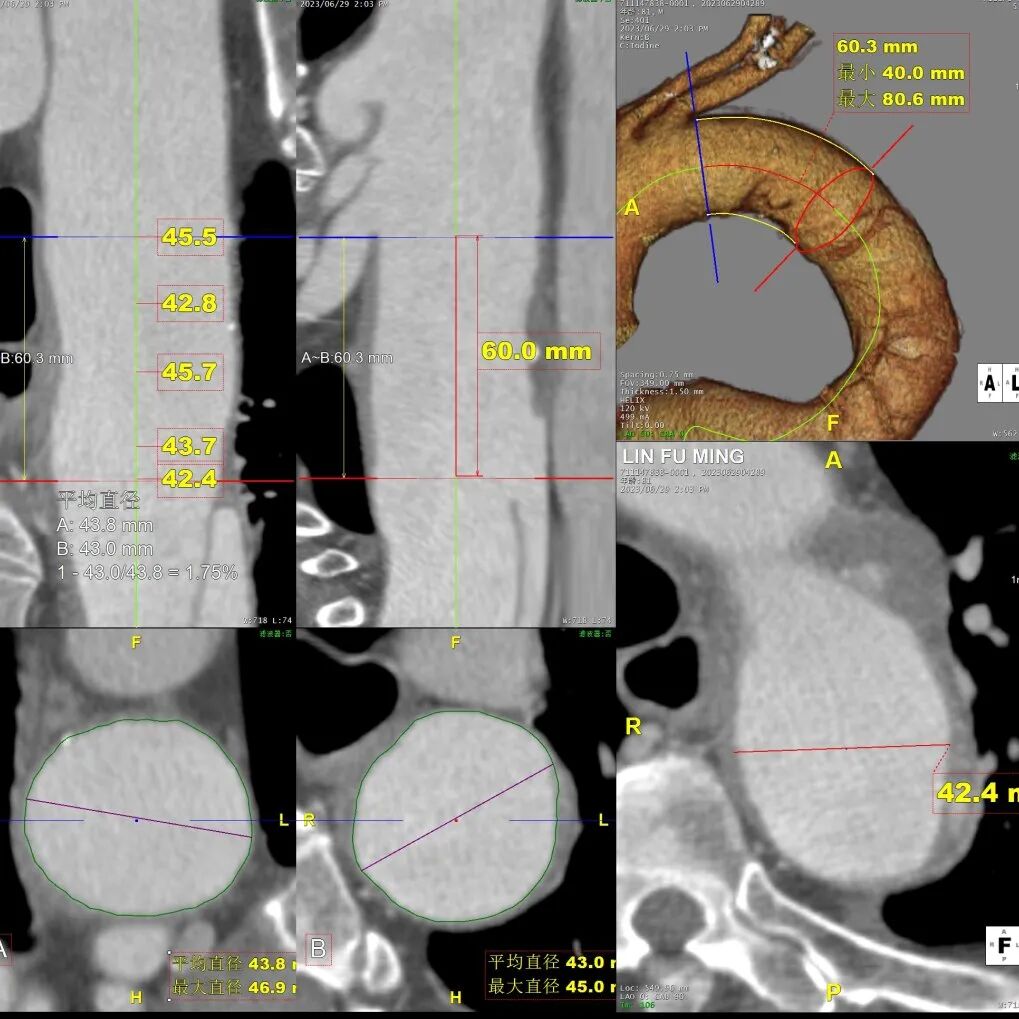

病例CTA详解

横断面影像

3)LSA起始部平均直径43mm+,降主段多发破口,真腔狭窄。